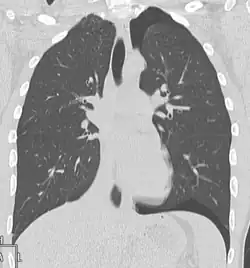

Verletzungen der Lunge können neben einer Lungenkontusion als Quetschverletzung Lungenrisse sein. Letztere führen zu einem Pneumothorax, wie er bei 10 bis 50 Prozent der Patienten mit Thoraxtrauma auftritt,[6] und gegebenenfalls zu einem Spannungspneumothorax. Blutungen in den Thorax hinein führen zu einem Hämatothorax. Bei einem Hämatopneumothorax treten sowohl ein Pneumo- als auch ein Hämatothorax in Kombination auf. Symptome sind zunächst Luftnot und je nach Ausmaß der Blutung auch Kreislaufinstabilität. Bei einem Pneumothorax kann sich insbesondere bei Ausbildung eines Spannungspneumothorax ein Hautemphysem bilden, das eine große Ausdehnung erreichen kann. Therapie ist eine Entlastung der Pleurahöhle mittels Thoraxdrainage auf der betroffenen Seite. Üblicherweise kommen kleinere intrathorakale Blutungen von alleine zum Stehen, so dass außer einer Drainage keine weiteren Maßnahmen notwendig werden. Eine Thorakotomie zur operativen Blutstillung kann bei einem initialen Blutverlust von mehr als 1.500 ml nach der Thoraxdrainage oder bei einem fortwährenden Blutverlust von mehr als 250 ml pro Stunde über mehr als vier Stunden erfolgen.[2][5]